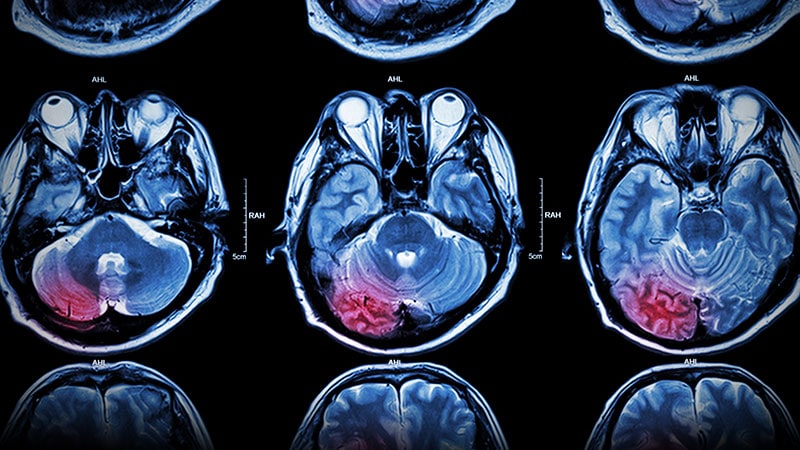

Taking ICH Cases Straight to Endovascular Center May Cause HarmRACECAT trial results suggest the longer travel times to the comprehensive stroke center -- rather than going to a closer

primary stroke center -- could be harmful for patients having a hemorrhagic stroke.